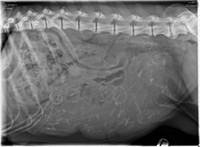

Sie befinden sich hier: Home Fotoalben Würfe S-Wurf Ultraschall + Röntgen